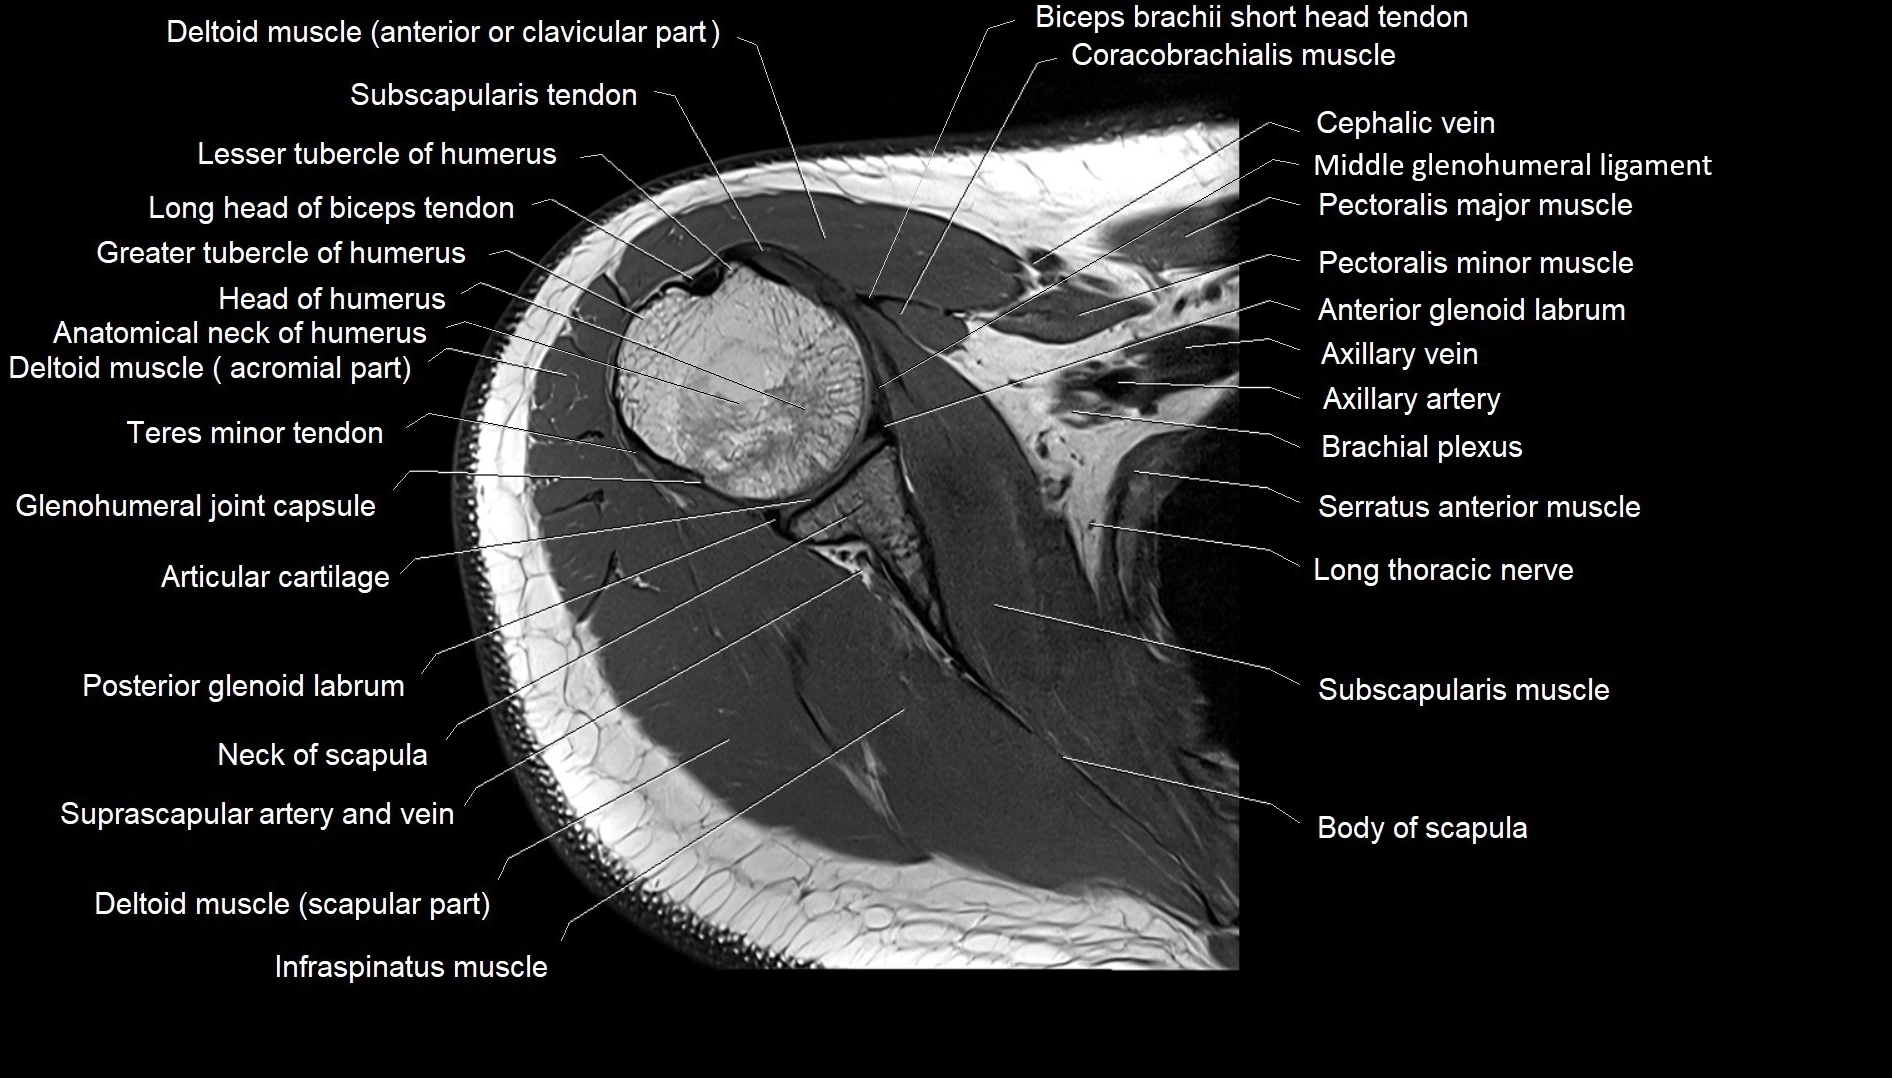

MRI images

image